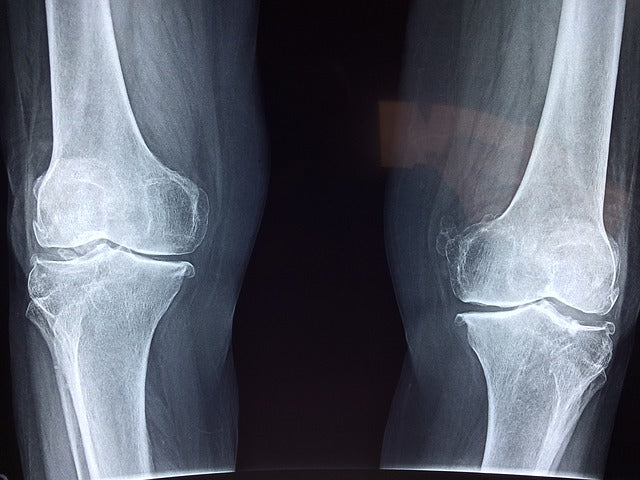

The result was a nightmare beyond imagining: Sandi had never broken a bone in her life, but after 7+ years of taking Fosamax, she suffered a fractured sacrum, vertebra and multiple pelvic fractures, not due to any traumatic stress, but simply from the weight of her own body. The excruciating pain incapacitated her for over a year, exacerbated by the failure of her health team to properly identify what was happening to her, despite outright evidence on x-rays and MRIs. The lesson here: long-term use of Fosamax (a bisphosphonate) can result in fragile bones that can fracture easily in a small percentage of people.

Another important note is that there are many people who have normal bone density or osteopenia who break bones easily (low-trauma fractures). When this happens we know that something else—other than bone density—is at play, and that is bone quality. This is why two people can have the same bone density, but one breaks bones easily, while the other has never broken a bone. Poor quality bone can be the result of poor nutrition, years of smoking or alcohol abuse, gastrointestinal disorders that result in malabsorption and, as mentioned above, prolonged use of some osteoporosis medications.